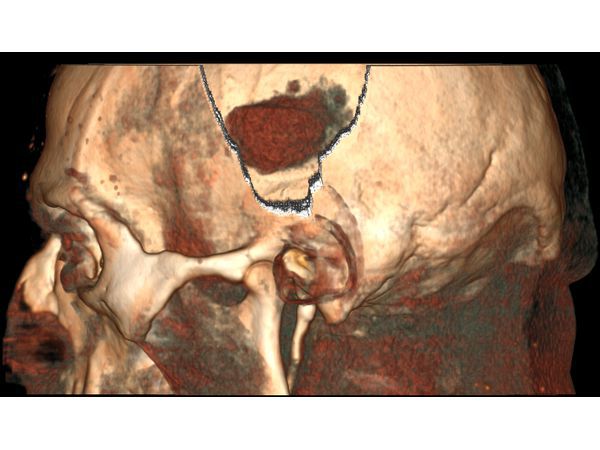

На следующий день пациенту выполнена краниотомия (трепанация черепа) и удаление инсульт-гематомы:

⠀• выполнен линейный разрез мягких тканей в левой височной области 5,0 см, скелетирована кость;

⠀• наложены три фрезевых отверстия, из которых резекционно сформировано трепанационное окно диаметром 3,5 см;

На следующий день после операции выполнен КТ-контроль: в области трепанации черепа видны костные фрагменты — костная стружка, уложенная в трепанационное окно при закрытии раны.